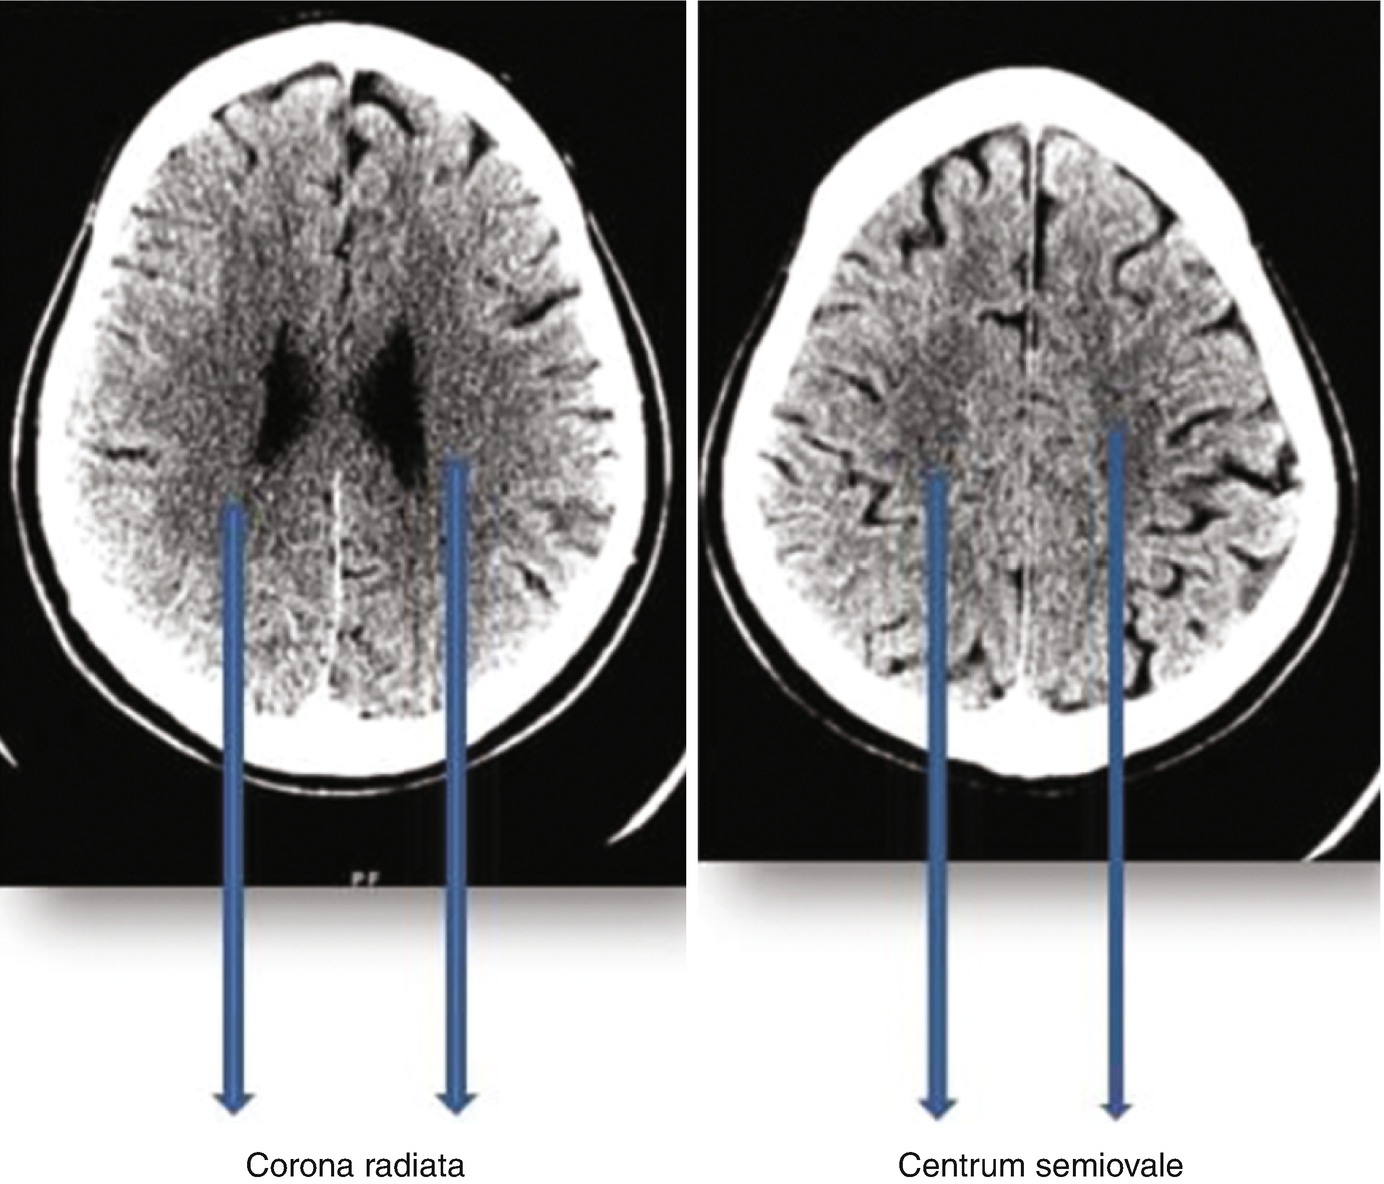

Corona Radiata Vs Centrum Semiovale

Multiple Calcifications In Bilateral Centrum Semiovale Corona Radiata Download Scientific Diagram